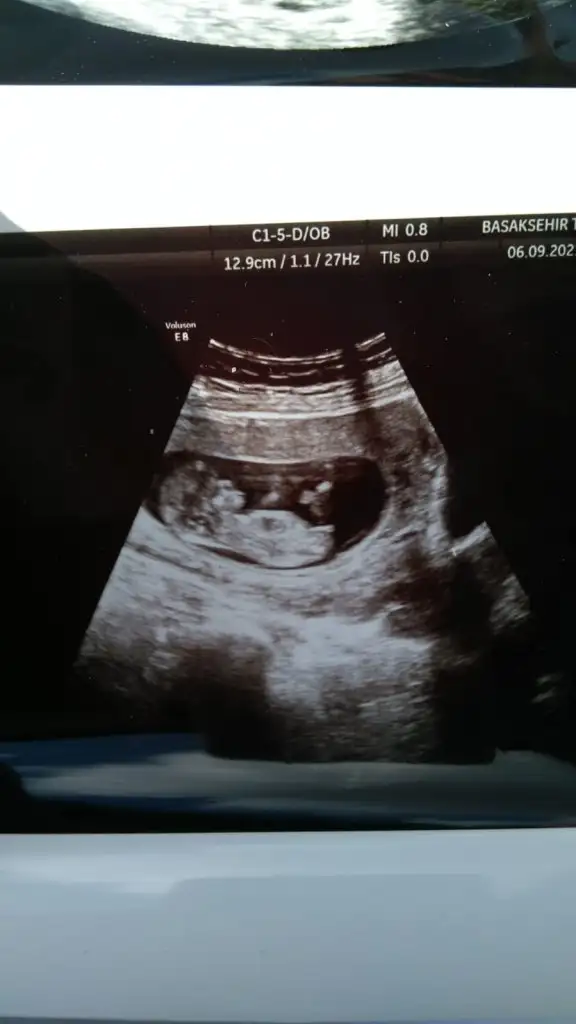

• IMG-20210906-WA0005.webp

IMG-20210906-WA0005.webp

23,6 KB · Görüntüleme: 107

Merhaba canım doktor kordon mu erkek mi karar veremedi 2 hafta sonra bi daha gel dedi başta erkek diyecektim sonra kordon olduğunu anladım dedi kesin bişey diyemiyorum dedi sen bi bakabilir misin 🥺🙏🏻🙏🏻♥️♥️♥️ Ikra meyra Ikra meyra Ikra meyra Ikra meyra